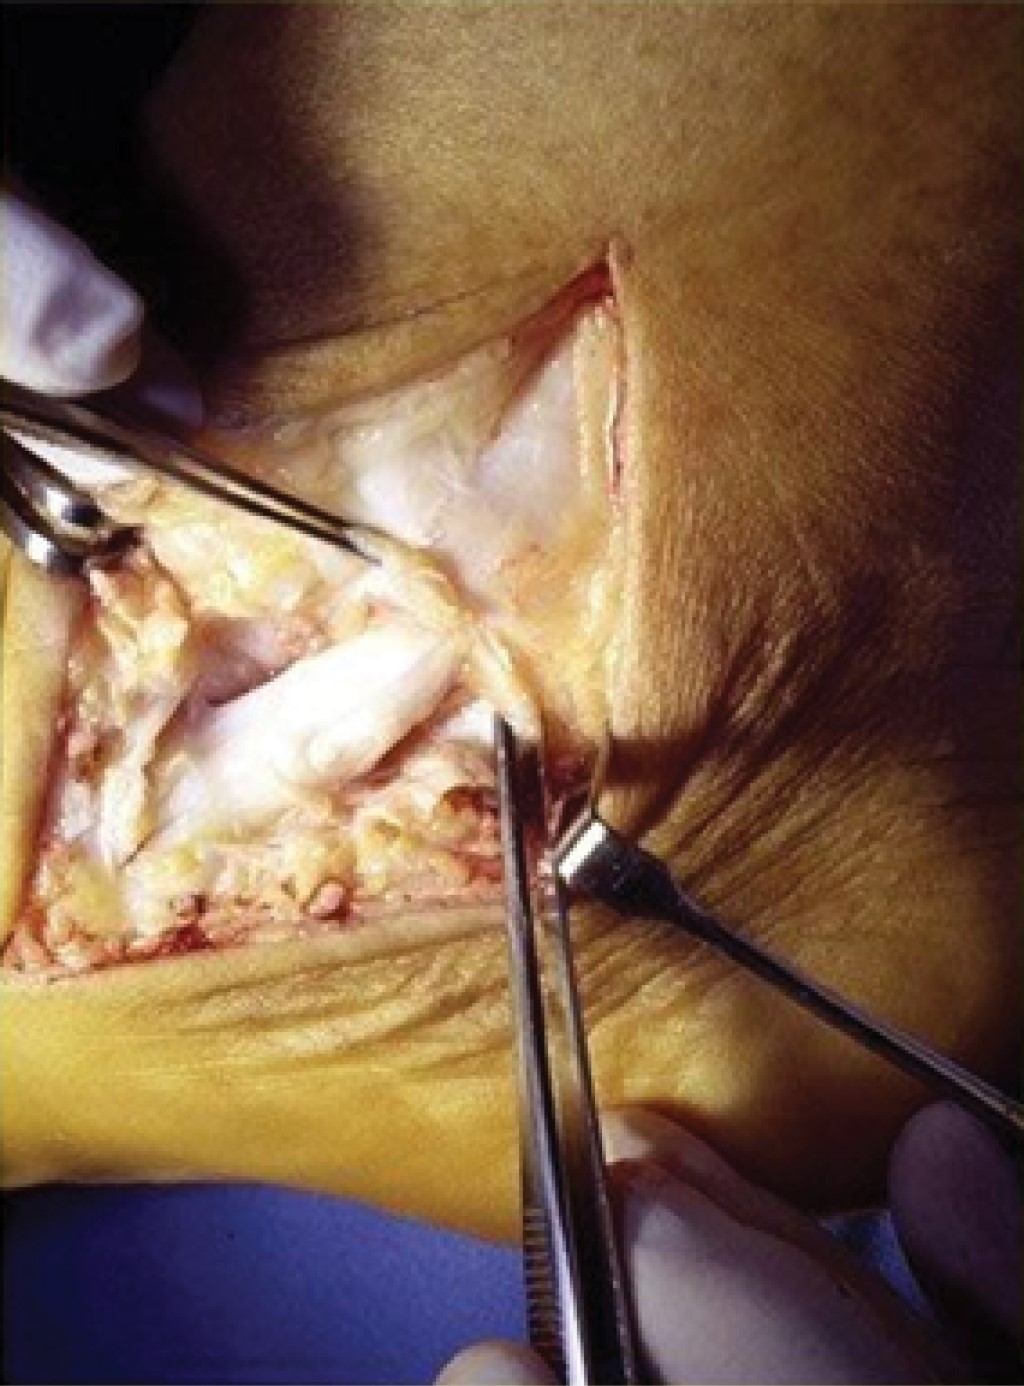

Figure 2